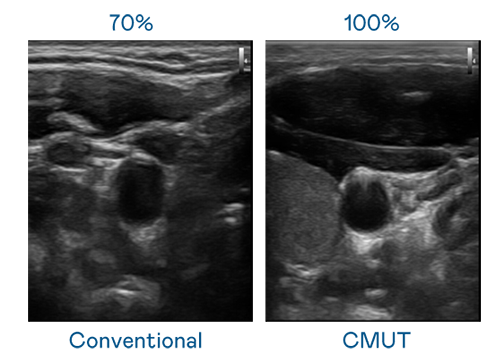

CMUT 技术是一种用电容式微机电元件来产生超音波讯号的技术。与传统 PZT 压电式技术相比,CMUT 频宽增加 30%,更宽频的超音波讯号让影像解析度大幅提升,是实现高影像品质医疗超音波扫描、促进精准医疗发展的关键技术。

超音波影像的解析度高低,首先取决于探头能发出的讯号频宽。CG电子 CMUT 可提供高清晰的超音波讯号,提供高频宽、高灵敏度、影像纹理细节更高的超音波影像,协助医护人员缩短影像判读时间及利用精准的医疗影像进行诊断。